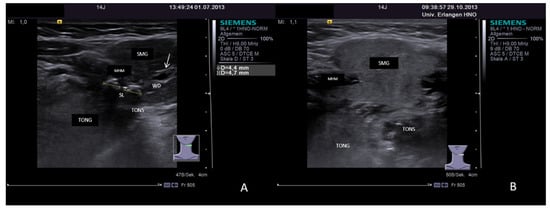

3.3.2. Obstructive Sialadenitis Caused by Sialolithiasis